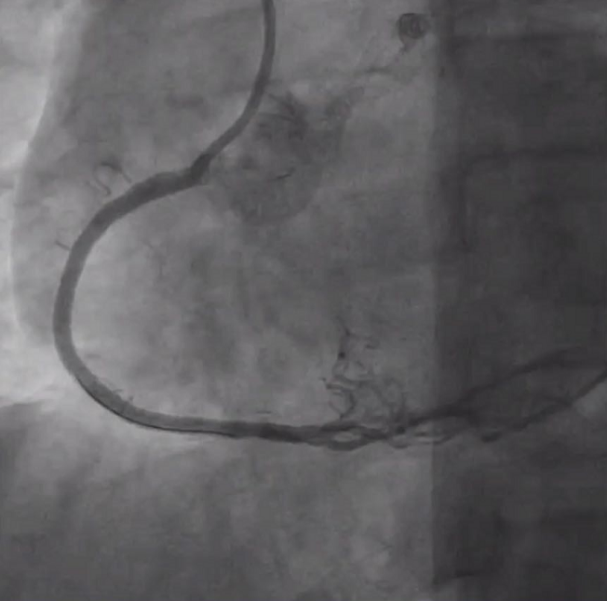

分析病变特征后术者决定首先启动正向策略,在Corsair微导管支撑下导丝进入内膜下,换用SASUKA导管辅助后通过平行导丝技术将Conquest pro导丝送入真腔,但无法通过RCA 3段重度狭窄处,在旋转Corsair时Corsair头端损毁并抱紧导丝。随后术者换用新的微导管和导丝,多次尝试后最终成功将1.0*10mm Firefighter™球囊送入闭塞段以远,以16atm反复扩张后球囊爆裂,为后续器械通过打开了通道。最终成功在闭塞段植入2枚支架。

RCA自近段闭塞

RCA植入支架后

对于这一病例,广东省人民医院杨峻青教授认为RCA异位开口导致强支持的Guiding难以到位。术者合理使用各种技术,配合合理的器械选择,很好完成手术。小尺寸的Firefighter™球囊通过性好,多次扩张后仍保持优越性能,帮助手术成功。